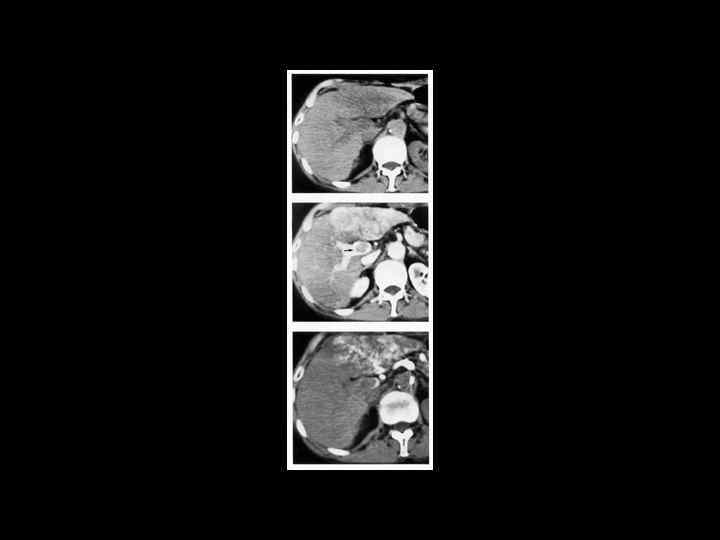

АКТУАЛЬНЫЕ ВОПРОСЫ РЕНТГЕНОЛОГИИ ЛУЧЕВАЯ ДИАГНОСТИКА ОЧАГОВЫХ ПОРАЖЕНИЙ ПЕЧЕНИ КАВЕРНОЗНАЯ ГЕМАНГИОМА Компьютерно-томографическая семиотика: - ограниченный участок пониженой плотности (до 50 -30 ед Н) - границы могут быть ровными, но нечеткими - после введения РКВ - характерный феномен усиления плотности от периферии к центру в течении нескольких минут после внутривенного введения РКВ

Клиническое наблюдение. Пациентка С. , 1953 г. р.

Та же пациентка